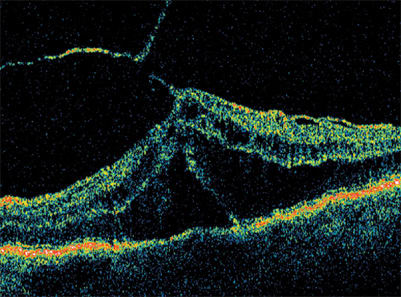

Using the Stratus OCT is an excellent way determine that subclinical posterior hyaloid traction is the cause of tractional retinal detachment and diabetic macular edema. Note the tent-like appearance of the tractional retinal detachment. Surgery is the best treatment choice.

The Stratus OCT is also useful for visualizing the several types of retinal detachments associated with DME. Serous detachments, which appear more concave in shape, generally respond well to steroid treatment. However, tractional retinal detachments, which have a tent-like appearance, do not respond to medical therapy. For any improvement to occur, the hyaloid must be surgically removed.